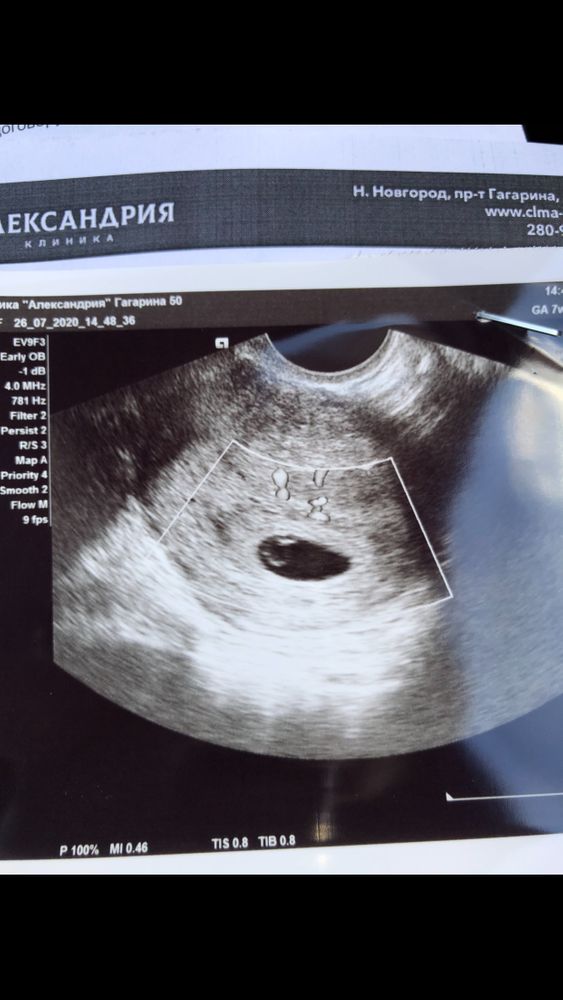

5 неделя беременности температура 38